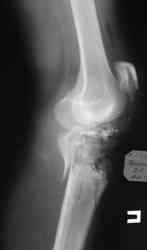

Уважаемые коллеги! На консультацию обратилась женщина, 23 года. В феврале огнестрельное ранение колена. Снимки первичные и майские в приложении. А также внешний вид раны. Укорочения конечности нет. Разгибание в коленном суставе отсутствует. Сгибание сохранено. Нестабильности нет.Дно раны - мертвая кость.

по снимкам у пациентки на данный момент сохраняется дефект наружного мыщелка б\б кости, который со временем приведет к вальгусной дефеормации голени и в настоящий момент практически отсутствует бугристость б\б кости, т.е. зона прикрепления собвственной связки, которую можно в принципе выкроить из средней порции сухожилия 4-хглавой со средней частью надколенника, но сначала необходимо запонить дефект костной ткани, либо путем свободной кости пластики, либо формированием отщепа б\б кости с микродистракцией в КДА Илизарова. т

В клинических снимках вроде достаточно мягких тканей, и возможно закрытие дефекта кожи местным ротационным методом. При возникновении трудностей тогда необходимо применить мышечную пластику. Без

восстановления мягкотканого футляра будут трудности со сращением кости. Мышечную пластику можно совместить с одномоментной кожной пластикой.